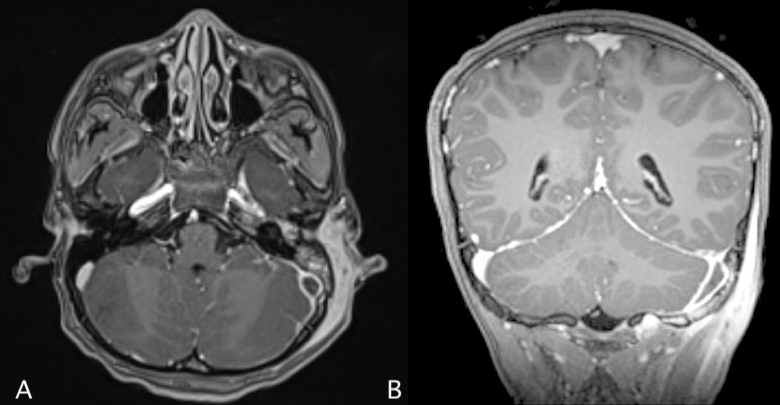

Upon arrival to the Emergency Department, the patient was non-toxic appearing and in no acute distress with normal vital signs for age (HR 97, BP 108/55, T 37.7C, RR 20, and SpO2 100% on room air). Physical examination was notable for proptosis of the left ear and a considerable amount of purulent drainage obstructing visualization of the left tympanic membrane. There was also fluctuant swelling and associated tenderness of the left mastoid without overlying erythema, induration, or warmth (Figure 2).

The patient had bloodwork completed, which was significant for leukocytosis to 15.5 (ref range: 4.5–13.5 103/μL) with a left shift and elevated CRP to 32.8 (ref range: 0.0 - 8.2 mg/L). CBC also demonstrated a normocytic anemia with Hgb 9.3 (ref range: 11.5 – 15.5 g/dL), and CMP was notable for mild hypoalbuminemia of 2.6 (ref range: 3.2 – 4.7 g/dL), but labs were otherwise unremarkable. He was started on empiric IV Ampicillin-Sulbactam (Unasyn). While awaiting transfer to a pediatric facility, the patient underwent a CT temporal bone with/without contrast, which revealed the following (Figure 3).